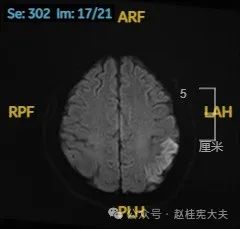

头颅磁共振平扫提示左侧颞枕叶亚急性期脑梗死可能。头颈部CTA示左侧椎动脉颅内段发育不良。头颅磁共振增强+波谱分析提示左侧颞枕叶病灶,考虑脑炎可能大。

入院后给予精氨酸,左卡尼丁,辅酶Q10,维生素E等治疗。患者病情稳定好转中,2天后意识清楚,语言表达仍欠佳。当天复查颅脑磁共振如下:

以上为患者发病后3次的颅脑磁共振片子,临床诊断基本上可以确认了,希望患者逐渐恢复!